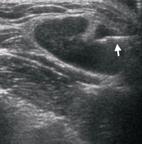

頭頸部軟組織超音波除了影像檢查外,還可以進行超音波導引下細針穿刺 (圖一),醫師會請病患平躺在治療檯上,肩下墊一枕頭,採頭部後仰及頸部伸展的姿式。用超音波檢查頸部腫塊後,再用空針於超音波導引下,穿過皮膚抽取腫塊內的細胞或體液並送化驗。穿刺後以酒精綿球或紗部壓迫止血約5至10分鐘即可。如此就可以獲得檢體檢查,往往進行超音波導引下細針穿刺細胞學檢查後就可以獲得診斷。相對於徒手進行的細針穿刺,超音波導引下細針穿刺可以目視細針在目標腫塊穿刺(圖一),因而確保檢體的品質。相較於徒手進行的細針穿刺約有三成的比例檢體品質不佳,超音波導引下細針穿刺約只有5% 的比例檢體品質不佳的比例,國際實證醫學研究報告指出,以超音波導引細針穿刺的確優於徒手進行的細針穿刺,對於小於3公分的腫瘤建議以超音波導引下細針。因此對於那些界限糢糊不清,徒手難以定位的頸部腫塊,超音波導引下細針穿刺是很好的檢查工具。

圖二、超音波導引下細針穿刺,可以目視細針(箭頭所指處)在目標腫塊穿刺,因而可確保檢體的品質